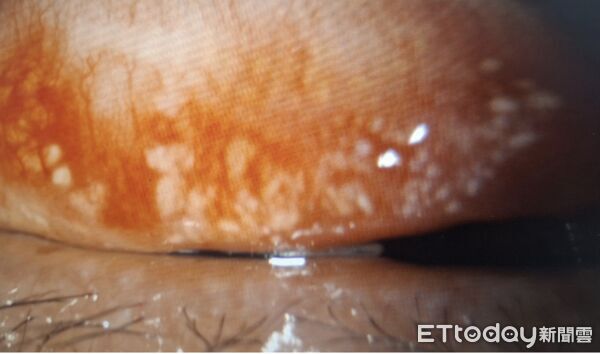

▲左上眼瞼內的眼結石,會撕裂角膜上皮細胞,而使視力缺損,初估約200顆。(圖/洪啟庭醫師提供)

進一步以裂隙燈檢查後,醫師發現患者上下眼瞼結膜內藏有大量眼結石,且分布相當密集,右眼上下眼瞼內各約數百顆,左眼上下眼瞼內也有大批眼結石,兩眼整體粗估接近千顆,由於部分結石已突出於結膜表面,患者每次眨眼時,都像有異物持續摩擦眼球表面,這也是造成疼痛、紅癢與角膜受損的重要原因。